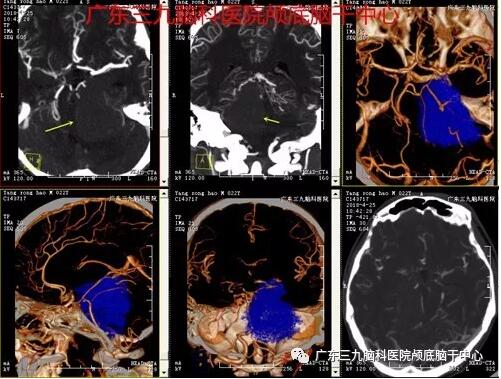

▲图3:头部CTA检查:1.右侧桥小脑角区-环池占位性病变血供不丰富,与基底动脉及右侧大脑后动脉关系密切;2.右侧椎动脉明显细小,考虑发育变异

▲图4:术后MR报告:左侧颞底占位病变切除术后改变,原病变已切除